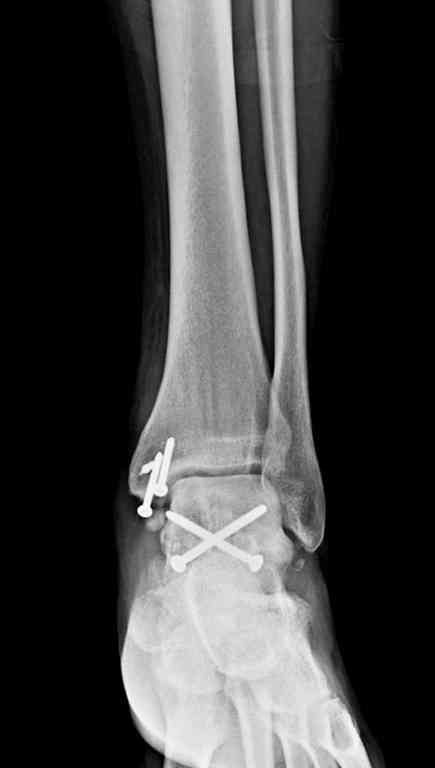

Из-за многооскольчатости дистальной части малоберцовой, где невозможно было провести фиксацию шурупами, перелом зафиксирован подпирающей пластиной, которая должна служить дополнением отсутствующей дистальной части малоберцовой (lateral cortex substitute).

Для стабильности два шурупа на синдесмоз.

Медиальную рану с приближенными краями продолжаем вакуумировать (KCI). Наружный фиксатор оставлен на пару недель, надеюсь, небольшая рана будет гранулировать и закроется без кожной пластики. Фиксация медиальной ложыжки не планируется.